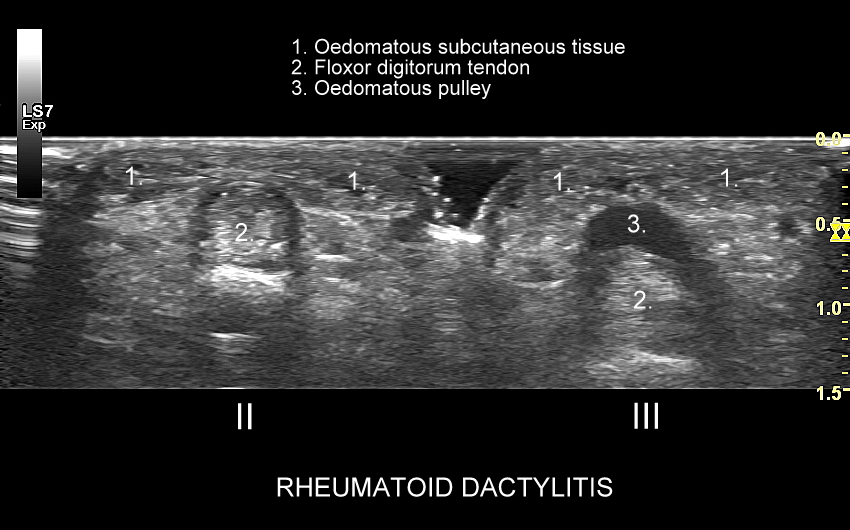

Badanie USG jest podstawową metodą diagnostyczną nadgarstka, ręki oraz palców. Pozwala z łatwością ocenić nerw pośrodkowy, więzadła, mięśnie, ścięgna, troczki, pochewki ścięgniste, stawy ręki i palców. Umożliwia zdiagnozowanie ukrytych złamań kości nadgarstka, śródręcza oraz palców. USG wykorzystuje się również w ocenie struktur po operacjach kanału nadgarstka. Spektrum przykładów chorób i patologii znajdowanych w USG ręki jest szerokie, a obejmuje m. in. zespół cieśni nadgarstka, zespół cieśni kanału Guyona, zespół de Quervaina, choroba Dupytrena, palec strzelający, kciuk narciarza, palec wspinacza, gangliony, kłębczaki podpaznokciowe i inne.

USG jest wysoce przydatną oraz metodą diagnostyczną pierwszego wyboru przy ocenie szeregu zmian chorobowych toczących się w obrębie stopy, w tym urazowych, przeciążeniowych, zapalnych, infekcyjnych, metabolicznych, czy nowotworowych. Przykładem najczęściej występującego urazu stopy, potocznie nazywanego skręceniem kostki występującego w wyniku inwersji stopy, jest naderwanie więzadła skokowo-strzałkowego przedniego (ATFL). Zmiany urazowo-przeciążeniowe dotyczyć mogą jednakże praktycznie każdego elementu. Dr Szczepański diagnozował w USG stopy m. in. takie patologie jak złamanie kości strzałkowej, złamanie trzeszczek, naderwania i zerwania ścięgien, czy przeciążenia troczków. W USG można ocenić również unaczynienie stopy, powikłania stopy cukrzycowej, zapalenie stawów w przebiegu dny moczanowej i reumatoidalnego zapalenia stawów, a także nowotwory stopy, w tym włókniaka rozścięgna podeszwowego (choroba Ledderhose’a).